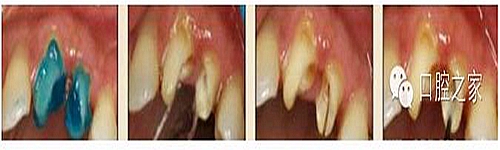

1.沖洗預(yù)備根管

大多數(shù)醫(yī)生在樁道預(yù)備時(shí)習(xí)慣于干燥預(yù)備根管(圖 1),這樣很容易破壞根管壁的牙本質(zhì)結(jié)構(gòu),同時(shí)也可形成較厚的玷污層,影響樹脂水門汀與牙體組織的粘接。因此,臨床操作時(shí)應(yīng)選擇沖洗的方法冷卻預(yù)備根管(圖 2),防止牙膠及封閉劑粘連附著于根管壁形成第二玷污層(根管治療時(shí)形成的玷污層稱為第一玷污層),有利于樹脂水門汀與根管牙本質(zhì)的粘接。

圖1:干燥預(yù)備根管。

圖2:沖洗預(yù)備根管。